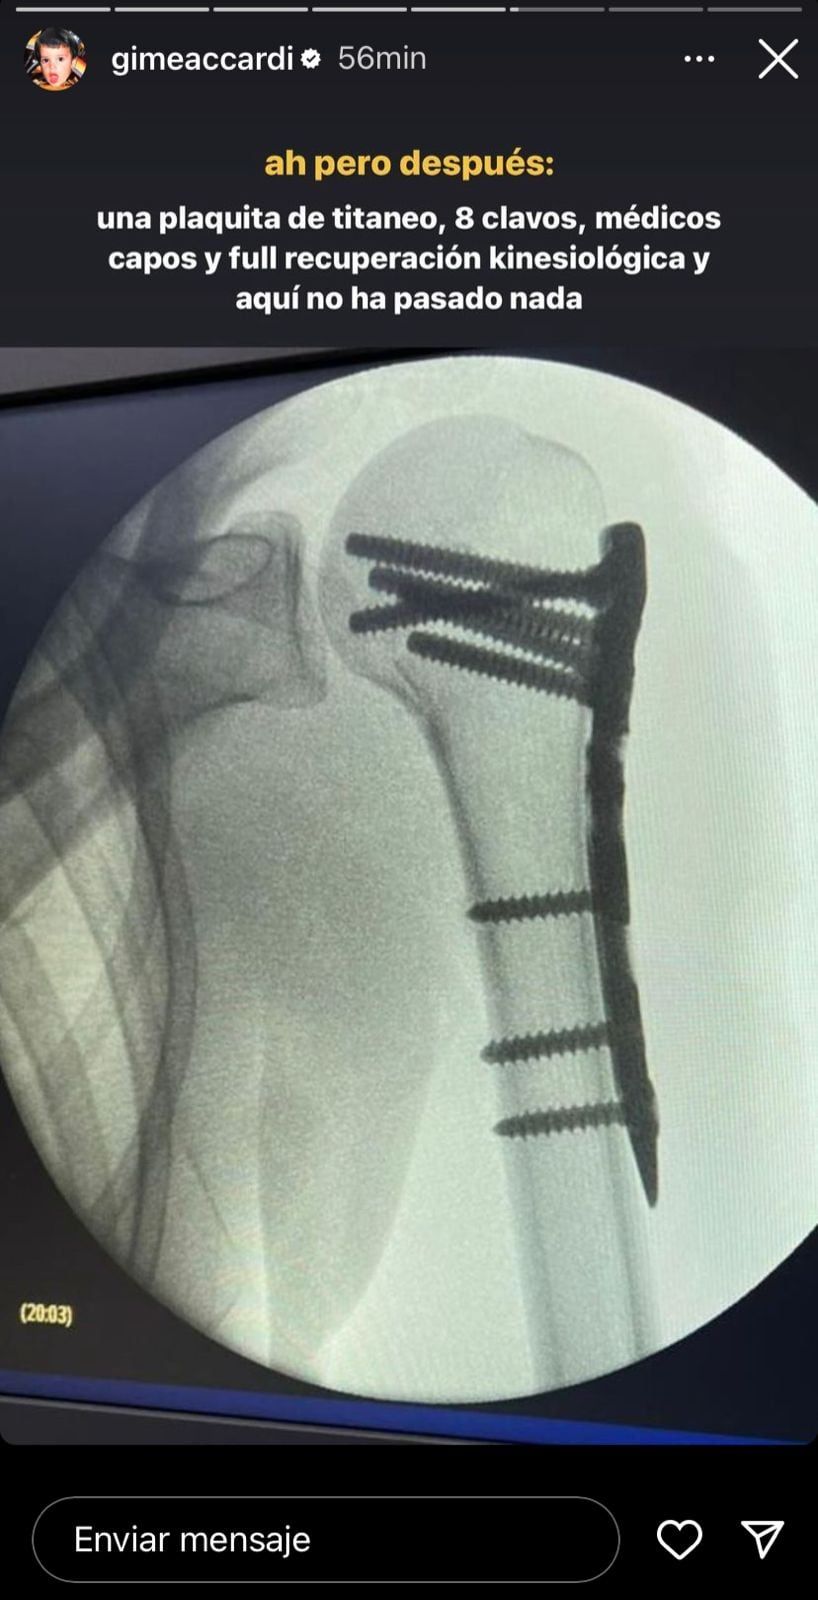

Por lo ocurrido, la artista debió someterse a una cirugía en el sanatorio de la Trinidad de San Isidro y el cirujano a cargo fue Pedro Hansing, el médico del plantel de River. Allí le colocaron una placa de titanio y ocho clavos, los que le permiten tener movilidad.

“Se cumplen dos años de mi operación de hombro, de esas cinco horas adentro de un quirófano reconstruyendo este hombro. Que por cierto, qué bien quedó. Y pensaba qué rápido pasa el tiempo y en ese momento sentía tanto tanto dolor y el brazo que no lo podía mover y pensé que nunca más lo iba a recuperar”, reveló la esposa de Nico Vázquez.

“Lo recuperé perfecto, el equipo médico que tuve fue un diez, pero no puedo creer que hoy esté así. Sin dolor prácticamente, salvo algunos días que duele un poquito”, contó sobre el proceso.